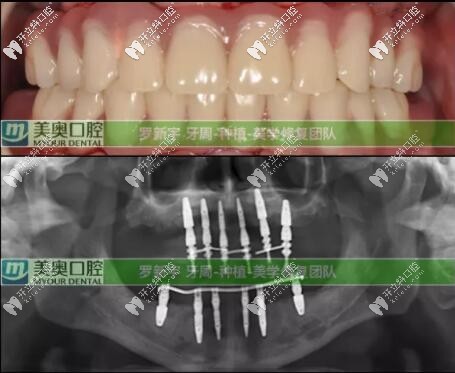

六個(gè)月后口腔檢查評(píng)價(jià):種植體全部存留、臨時(shí)修復(fù)體存留、終末修復(fù)體(長(zhǎng)久性的牙冠)存留;可以說(shuō)這次種植修復(fù)是很成功的。

經(jīng)過(guò)回訪(fǎng),顧客對(duì)全口種植牙的美學(xué)和效果很滿(mǎn)意,后期杭州美奧口腔還會(huì)進(jìn)行長(zhǎng)期的跟蹤回訪(fǎng)...